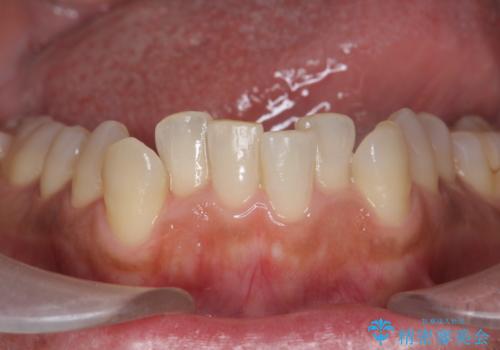

- マウスピース矯正中に、口臭が気になりクリーニングを行いたいとのことでした。染め出しをしての歯ブラシ指導とPMTC60分コースを行いました。

口腔内にはたくさんの細菌がいるため、ヌルヌルとしたプラーク(歯垢)が自然に歯の表面に付きます。

このプラーク(歯垢)にはたくさんの細菌が潜んでおり、虫歯や歯周病・口臭などの最大の原因です。そのため、毎日の歯磨きでプラーク(歯垢)をキレイに取り除くことが、健康な歯を保つためには欠かせません。

しかし、プラークは歯の色と似ているため、見ただけでは付着しているかどうかがハッキリとは分かりません。

染め出し液を使ってプラークを染め出すことにより、普段の歯みがきで磨き残している場所を目で確かめることができます。

日々の歯磨きを上達するには、まずどこが磨けていないか認識することが大切です。